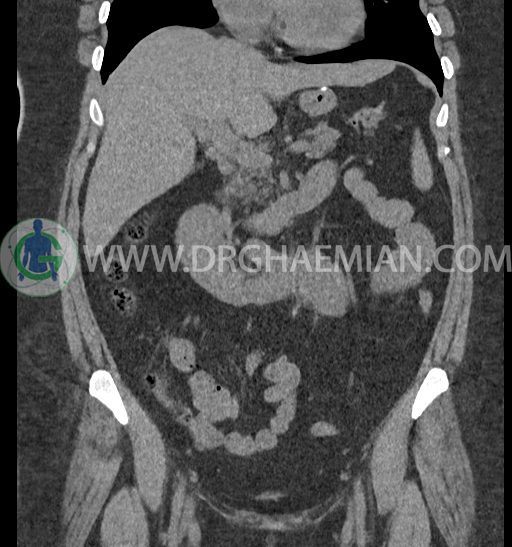

سی تی اسکن شکم و لگن با استفاده از اشعات ایکس تصاویر عرضی از ناحیه شکم و لگن ایجاد میکند. در این کیس کلیه نعل اسبی و سنگ کلیه مشاهده می شود.

در سی تی اسکن اسپیرال شکم و لگن بدون کنتراست (مولتی دیدکتور 16 با مقاطع ظریف و بازسازی های ساژیتال و کرونال) :

لنف آدنوپاتی در اطراف آئورت و IVC دیده نمیشود.

مایع آزاد در حفره شکم و لگن رویت نمی شود.

توده، کیست و collection مشهود نیست.

ضایعه ای در مثانه و حفره لگن مشهود نیست.

-horseshoe kidney

-حداقل سه سنگ 5mm در کلیه راست و یک سنگ 3mm در کلیه چپ بدون شواهدی از هیدرونفروز